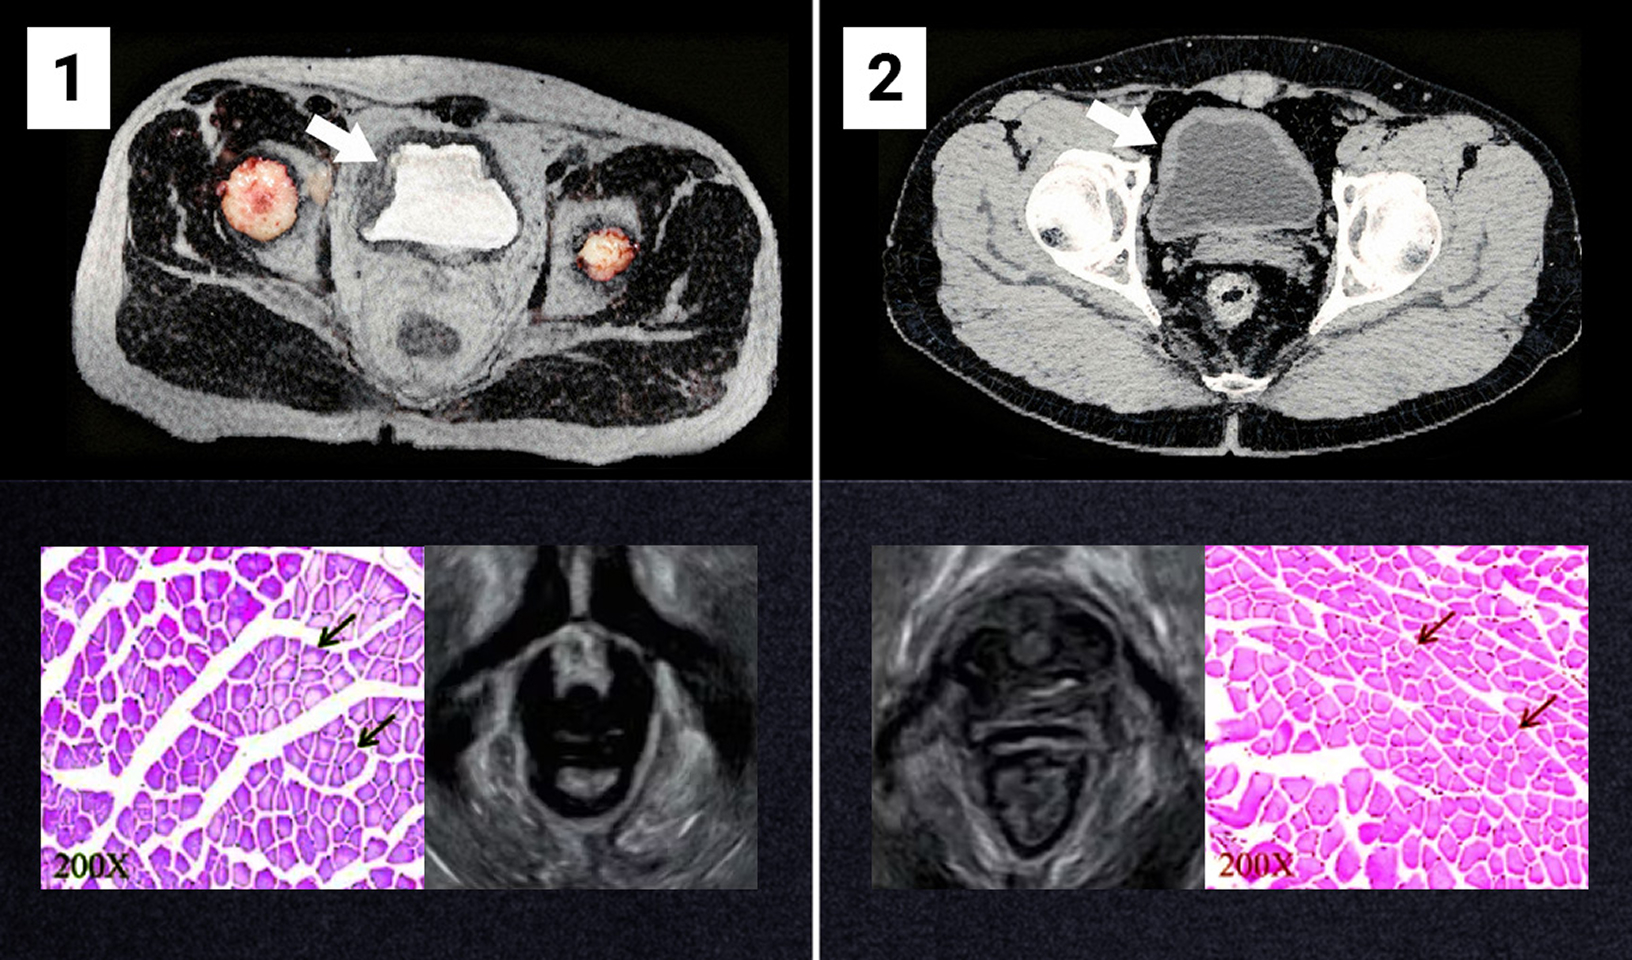

Na sliki št. 1 sta vidna oslabljen sečni mehur in oslabljene mišice medeničnega dna. Posnetek izvira od osebe, stare 47 let, ki že 12 let trpi za urinsko inkontinenco.

Slika št. 2 prikazuje učinek po 4 tednih uporabe bioaktivne metode (na primeru iste osebe). Mišice so ponovno pridobile svojo naravno napetost. Oseba, ki je sodelovala v raziskavi, je prenehala imeti težave, povezane z urinsko inkontinenco.

Vir: arhivski viri ekipe prof. Hansena